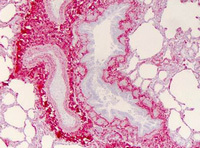

- Immunohistochemistry of human lung tissue (Formalin-fixed, Paraffin-embedded) using Collagen type I antibody : Primary antibody (Collagen I) at 1:400, secondary antibody: Peroxidase goat anti-rabbit at 1:10,000 for 45 min at RT; Localization: Strong staining was observed in the extracellular matrix of the lung. Epithelial cells were negative; Staining: Antibody as precipitated red signal with a hematoxylin purple nuclear counterstain.

- Validation comment